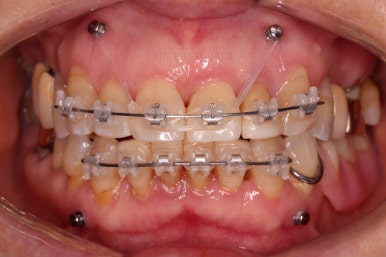

우선 장치를 부착하고요.

가지런하게 하면서 치간삭제 및 기존 떼워진 수복물을 제거한 뒤에 틈을 만들거나 모아줘요.

잇몸에서 주욱 빠져나와서 길어보이던 치아를 다시 잇몸 속으로 원위치 시키는 작업을 같이 해줘요.

점점 부산부분교정을 통해 가지런해지면서 틈새가 모이는 걸 볼 수 있어요.

치아가 없는 부분은 틀니도 병행해서 사용하셨고요.